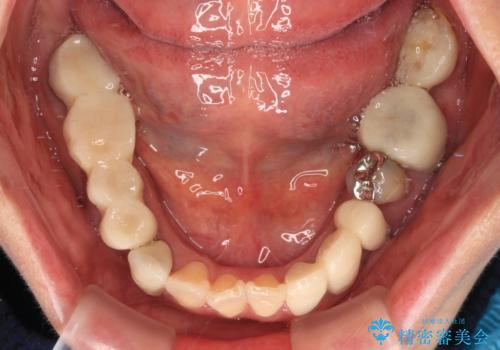

- 近医にて古いかぶせ物をセラミッククラウンにしようと治療を開始したものの、仮歯での咬み合わせが不安定とのことで、転院を希望して来院された患者様です。

骨格的に下顎骨が前方位に位置しており、上下前歯部の先端同士が接触する切端咬合でした。

このような方は咬み合わせが大きく変わると不安定となるため、まずは装着されている仮歯で咬合調整を行い、安定した咬み合わせとした後に、新しい仮歯に置き換え、その後オールセラミッククラウンにて補綴治療を行うこととしました。

仮歯で咬み合わせの調整を行ってからは、特に不安定になることもなく、非常にスムーズに治療を進めて行くことができました。

前歯奥歯ともに望ましくない力がかかりやすい咬み合わせであるため、就寝時にはマウスピースを使用するようにお伝えしております。